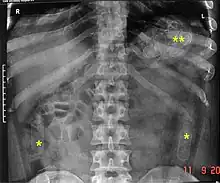

As cavity searches have proven as an ineffective strategy in the total prevention of smuggling objects as it cannot detect objects in the intestines or stomach, as well as taking into consideration the intrusive nature and inherently humiliating or degrading procedure, it has become fairly normal for authorities to instead isolate individuals in a monitored environment until they pass excreta and/or x-ray the individual's pelvic area as it is less invasive and psychologically damaging.

Some inmates and human rights activists argue that body cavity searches are done not so much to stop the flow of contraband but rather to harass and humiliate detainees. A visual inspection of the rectum will not reveal objects concealed deeply inside. Likewise, it is possible to circumvent detection during manual body cavity searches. In some instances, suspects swallow packages of drugs protected by condoms and allow them to pass through their digestive tract. Only diagnostic imaging will reveal the concealed contraband, invalidating the body cavity search.